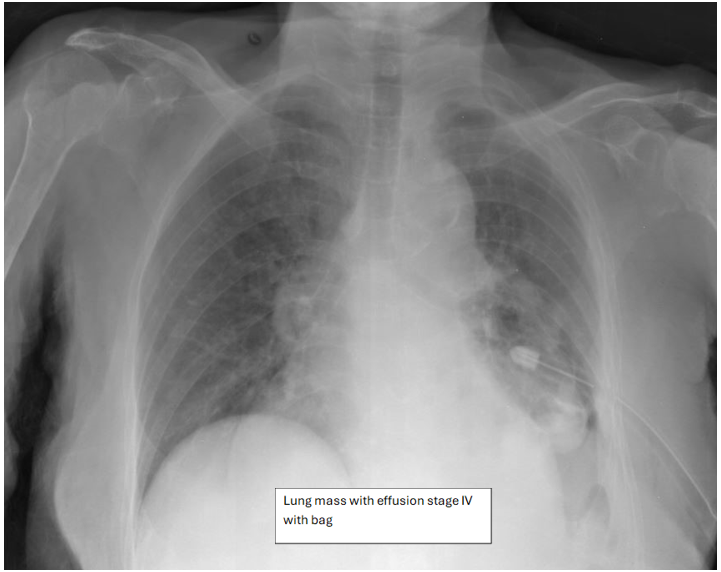

Figure 1

Figure 2

Figure 3

Figure 4

Figure 5

Figure 6

Figure 7